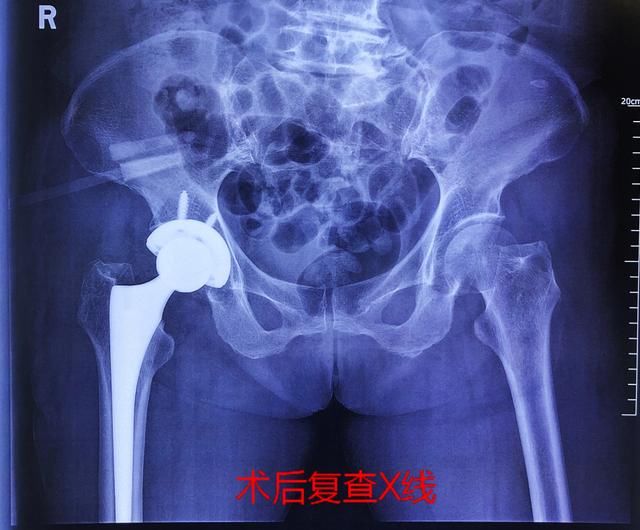

近日,家人将老人送至湖南中医药大学第二附属医院(湖南省中医院)骨伤三科,完善CT检查后确认黄奶奶“右侧股骨颈骨折”且股骨头已移位。因保守治疗效果不佳且易发生感染、血栓等并发症,由科主任、副主任医师董克芳教授率专家团队为黄奶奶施行右侧人工全髋关节置换手术,术后第二天黄奶奶就能下地活动了,恢复良好。家人疑惑的是,老人家摔跤后前段时间都还好像问题不大,怎么突然就成骨折了呢?